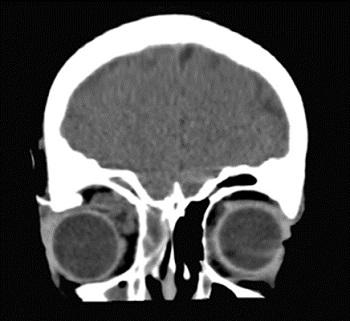

Caso 1. Niño de 8 años que ingresa por cuadro de sinusitis que no mejora a pesar de recibir antibioterapia por vía oral. Al cuarto día de tratamiento antibiótico intravenoso con amoxicilina-clavulánico, presenta crisis convulsivas generalizadas de breve duración. Se realiza una prueba de imagen que evidencia la presencia de empiema subdural y pansinusitis (Fig. 1). A la exploración, presenta Glasgow 15, leve hemiparesia izquierda y sensación de hiperestesia en la pierna del mismo lado. Se inicia tratamiento con cefotaxima, vancomicina y metronidazol y se realiza drenaje del empiema frontal mediante craneotomía, sin incidencias postoperatorias. Recibe tratamiento con gabapentina y levetiracetam, con el que mejora su dolor neuropático y se resuelven las crisis convulsivas. A los 10 días de la primera intervención, comienza con fiebre y disminución del nivel de conciencia, por lo que, ante el evidente empeoramiento clínico y radiológico (Fig. 2), se realiza segunda intervención quirúrgica con ampliación de la craneotomía inicial y drenaje interhemisférico del empiema y se sustituye el tratamiento con cefotaxima por meropenem en perfusión extendida. Se cultiva el material purulento drenado y se aísla Streptococcus intermedius. Tras cumplimentar seis semanas de tratamiento antibiótico intravenoso y tras objetivar mejoría de la imagen radiológica, el paciente es dado de alta sin secuelas, a excepción de una ligera paresia de la extremidad inferior izquierda evidenciada con la marcha autónoma.